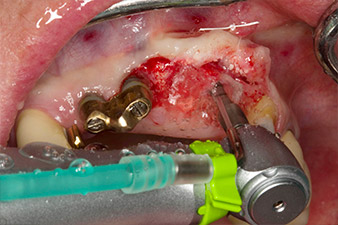

Dopo la prima guarigione, i tessuti molli sono stati sagomati con un ponte rivestito nella porzione basale. Due mesi dopo, il sito è stato esposto con una leggera incisione sula cresta palatoalveolare (Fig. 2). Si è visto che le dimensioni dell'osso alveolare erano sufficienti in corrispondenza della posizione 22. Le figure 2 e 4 mostrano la preparazione della sede di impianto, l'avvitamento e l'impianto utilizzando Implantmed.

Per compensare la perdita ossea periodontale e ottenere un risultato estetico piacevole, si è proceduto all'impianto unitamente alla rigenerazione guidata dell'osso (tecnica GBR) con materiale di riempimento xenogenico e membrana di collagene (Fig. 5 e 6).